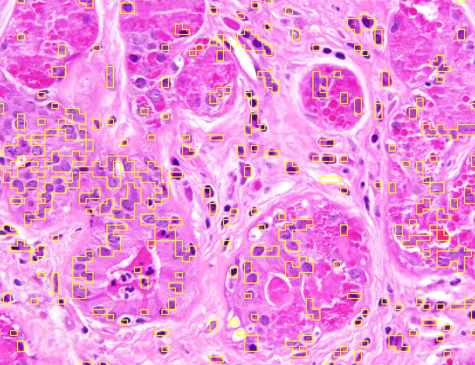

Dataset 1 comprises a synthetic video and two hematoxylin and eosin (H&E)-stained images collected from public online sources [71, 72]. H&E staining is standard in histopathology, with nuclei appearing blue–purple and cytoplasm pink. The images are provided in RGB format with varying image sizes and are used solely for qualitative illustration and timing comparisons, as no ground-truth annotations are available. The synthetic video consists of 74 MATLAB-generated frames. The first frame shows a 3D mitochondrial mesh generated via the isosurface function and rendered with Phong illumination, with the light source positioned above and to the right of the camera. Subsequent frames are obtained by rotating this initial view. This dataset was constructed to study segmentation under pronounced frame-to-frame illumination changes.

Representative samples from the three datasets are shown in Fig. 1. In (a), the first frame of the synthetic video in Dataset 1 illustrates the strong illumination gradients produced by distance-dependent shading together with orientation-dependent interactions between vertex normals and the light direction. The H&E images in (b) and (c), also from Dataset 1, depict a mast cell infiltrate from a patient with non-alcoholic steatohepatitis and cirrhosis and, respectively, a sample from a patient with sclerosing polycystic adenosis of the parotid gland; the former consists primarily of purple nuclei, white cytoplasm, and pink extracellular tissue. Subfigures (d) and (e) show two examples from Dataset 2 accompanied by their ground-truth nuclei annotations, while (f) and (g) present a representative image from Dataset 3 together with its corresponding cell mask.

Figure 1: Samples from Datasets 1–3. (a) First frame of the 74-frame video in Dataset 1 (1770 × 880) with a superimposed red mesh. (b,c) H&E-stained tissue images from Dataset 1 (1000 × 750; 950 × 730). (d,e) Cell images from Dataset 2 (600 × 600) with nuclei annotations. (f,g) Image from Dataset 3 (512 × 512) with annotation.